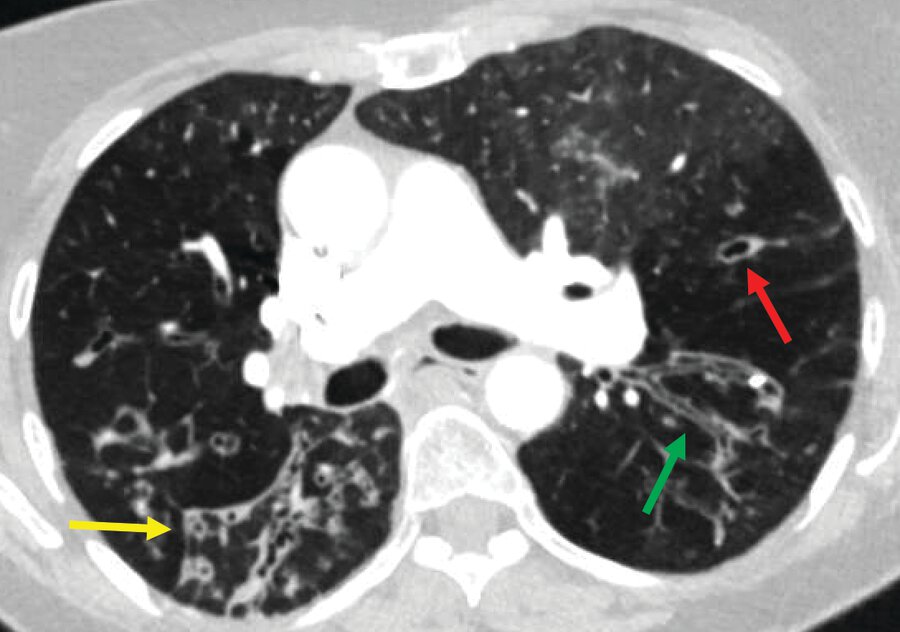

This diagnosis presents with airway dilation and often signet ring appearance. Name the diagnosis.

What is: bronchiectasis